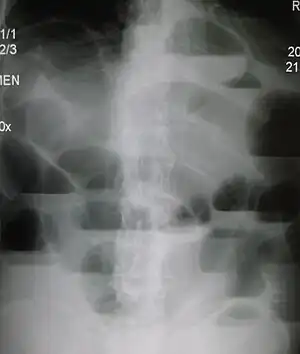

Radiological signs of bowel obstruction include bowel distension and the presence of multiple (more than six) gas-fluid levels on supine and erect abdominal radiographs. Ultrasounds may be as useful as CT scanning to make the diagnosis.[17]

Contrast enema or small bowel series or CT scan can be used to define the level of obstruction, whether the obstruction is partial or complete, and to help define the cause of the obstruction. The appearance of water-soluble contrast in the cecum on an abdominal radiograph within 24 hours of it being given by mouth predicts resolution of an adhesive small bowel obstruction with sensitivity of 97% and specificity of 96%.[18]

Most people with SBO are initially managed conservatively because in many cases, the bowel will open up. Some adhesions loosen up and the obstruction resolves. The patient is examined several times a day, and X-ray images are made to ensure he or she is not getting clinically worse.[29]